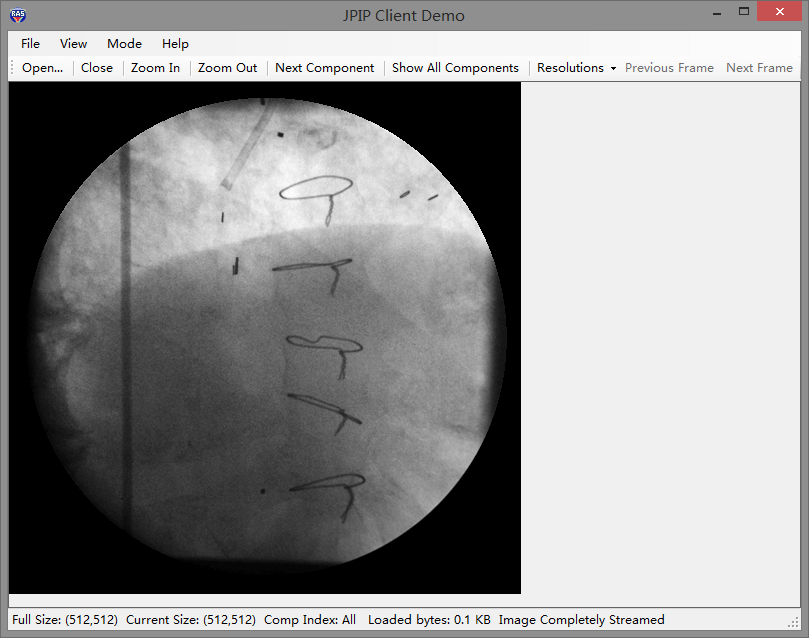

leadtools 完整的jpip协议,帮助您创建jpip 服务器和客户端,使您能够快速的开发出一个完整的切片工作站,各种细胞切片、组织切片都可以无延迟浏览。